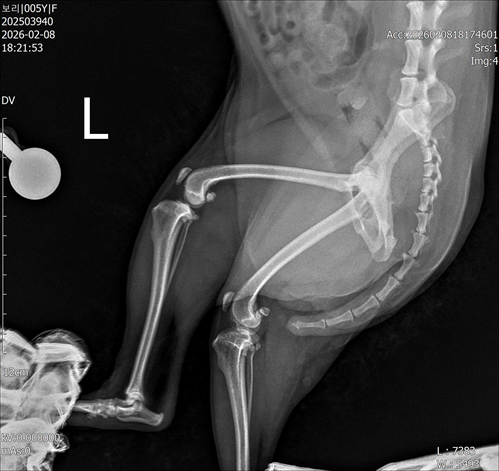

강아지 슬개골탈구 진단 받았습니다 몇군데 병원을 다녀봤는데 진단이 달라 궁금해서 질문 해봅니다 일단 저희 강아지는 오른쪽 다리를 갑자기 들고 다니고 절어 병원을 방문하게 되었고요 왼쪽은 증상이 없지만 오른쪽만 있는 상태였습니다 첫번째랑 두번째 병원에서는 슬개골 탈구 진행중이고 왼쪽이 3기 오른쪽이 2기 정도라고 했습니다 하지만 왼쪽은 아예 빠져있어 증상도 없고 아파하지도 않는다고 했고 오른쪽은 빠졌다 안빠졌다 해서 증상이 있다고 했고 십자인대가 파열된 걸론 보이지 않는다고 했습니다 그래서 양쪽 슬개골탈구 수술만 진행하면 된다고 했고요 근데 세번째 병원에서는 둘다 왼쪽이 좀 더 심한 슬개골 탈구 3기 정도라고 했고 오른쪽만 십자인대 부분파열이 보인다고 했습니다 그래서 십자인대 파열이 아닌 왼쪽은 굳이 수술할 필요가 없고 나중에 십자인대 파열이 오거나 증상이 나타나면 그때 수술하면 된다고 했습니다 그래서 오른쪽 슬개골탈구 수술과 tplo를 하는 방식으로 수술을 한다고 했습니다 여기서 궁금한점은